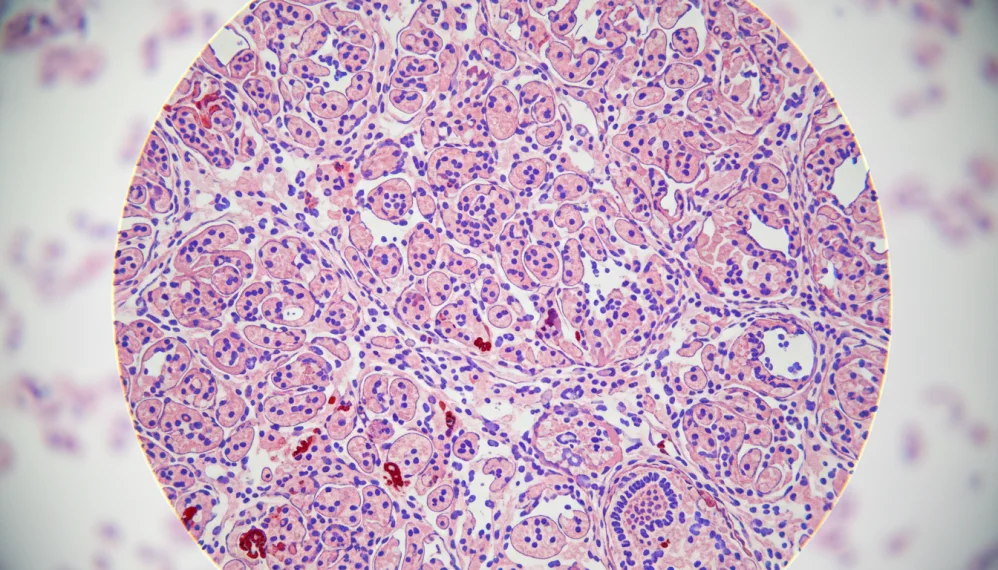

Tesutul care captuseste uterul se numeste endometru. In timpul fiecarui ciclu menstrual are loc o crestere, in volum a endometrului, o ingrosare, acesta pregatindu-se pentru o posibila sarcina. In cazul in care femeia nu ramane insarcinata, endometrul se elimina in asa numita perioada menstruala. Endometrioza se defineste ca fiind tesutul endometrial care creste in afara uterului (in afara localizarii normale). De obicei apare la nivelul ovarelor, a trompelor uterine, in afara suprafetei uterului, la nivelul intestinelor sau a altor organe abdominale. In situatii extrem de rare poate afecta alte organe si structuri din corp.

Endometrioza formata prin proliferarea (cresterea) endometrului este denumita "implant". Acestea cresc in volum, sangereaza si se elimina in timpul fiecarui ciclu menstrual ca un endometru "fals" existent. Acesta poate cauza durere si poate sa determine ca o femeie sa ramana insarcinata foarte dificil. In unele cazuri, in jurul acestor implante se formeaza tesut cicatricial. Tesutul cicatricial poate de asemenea sa cauzeze durere si probleme in a ramane insarcinata si poate interveni in functia normala a organului.